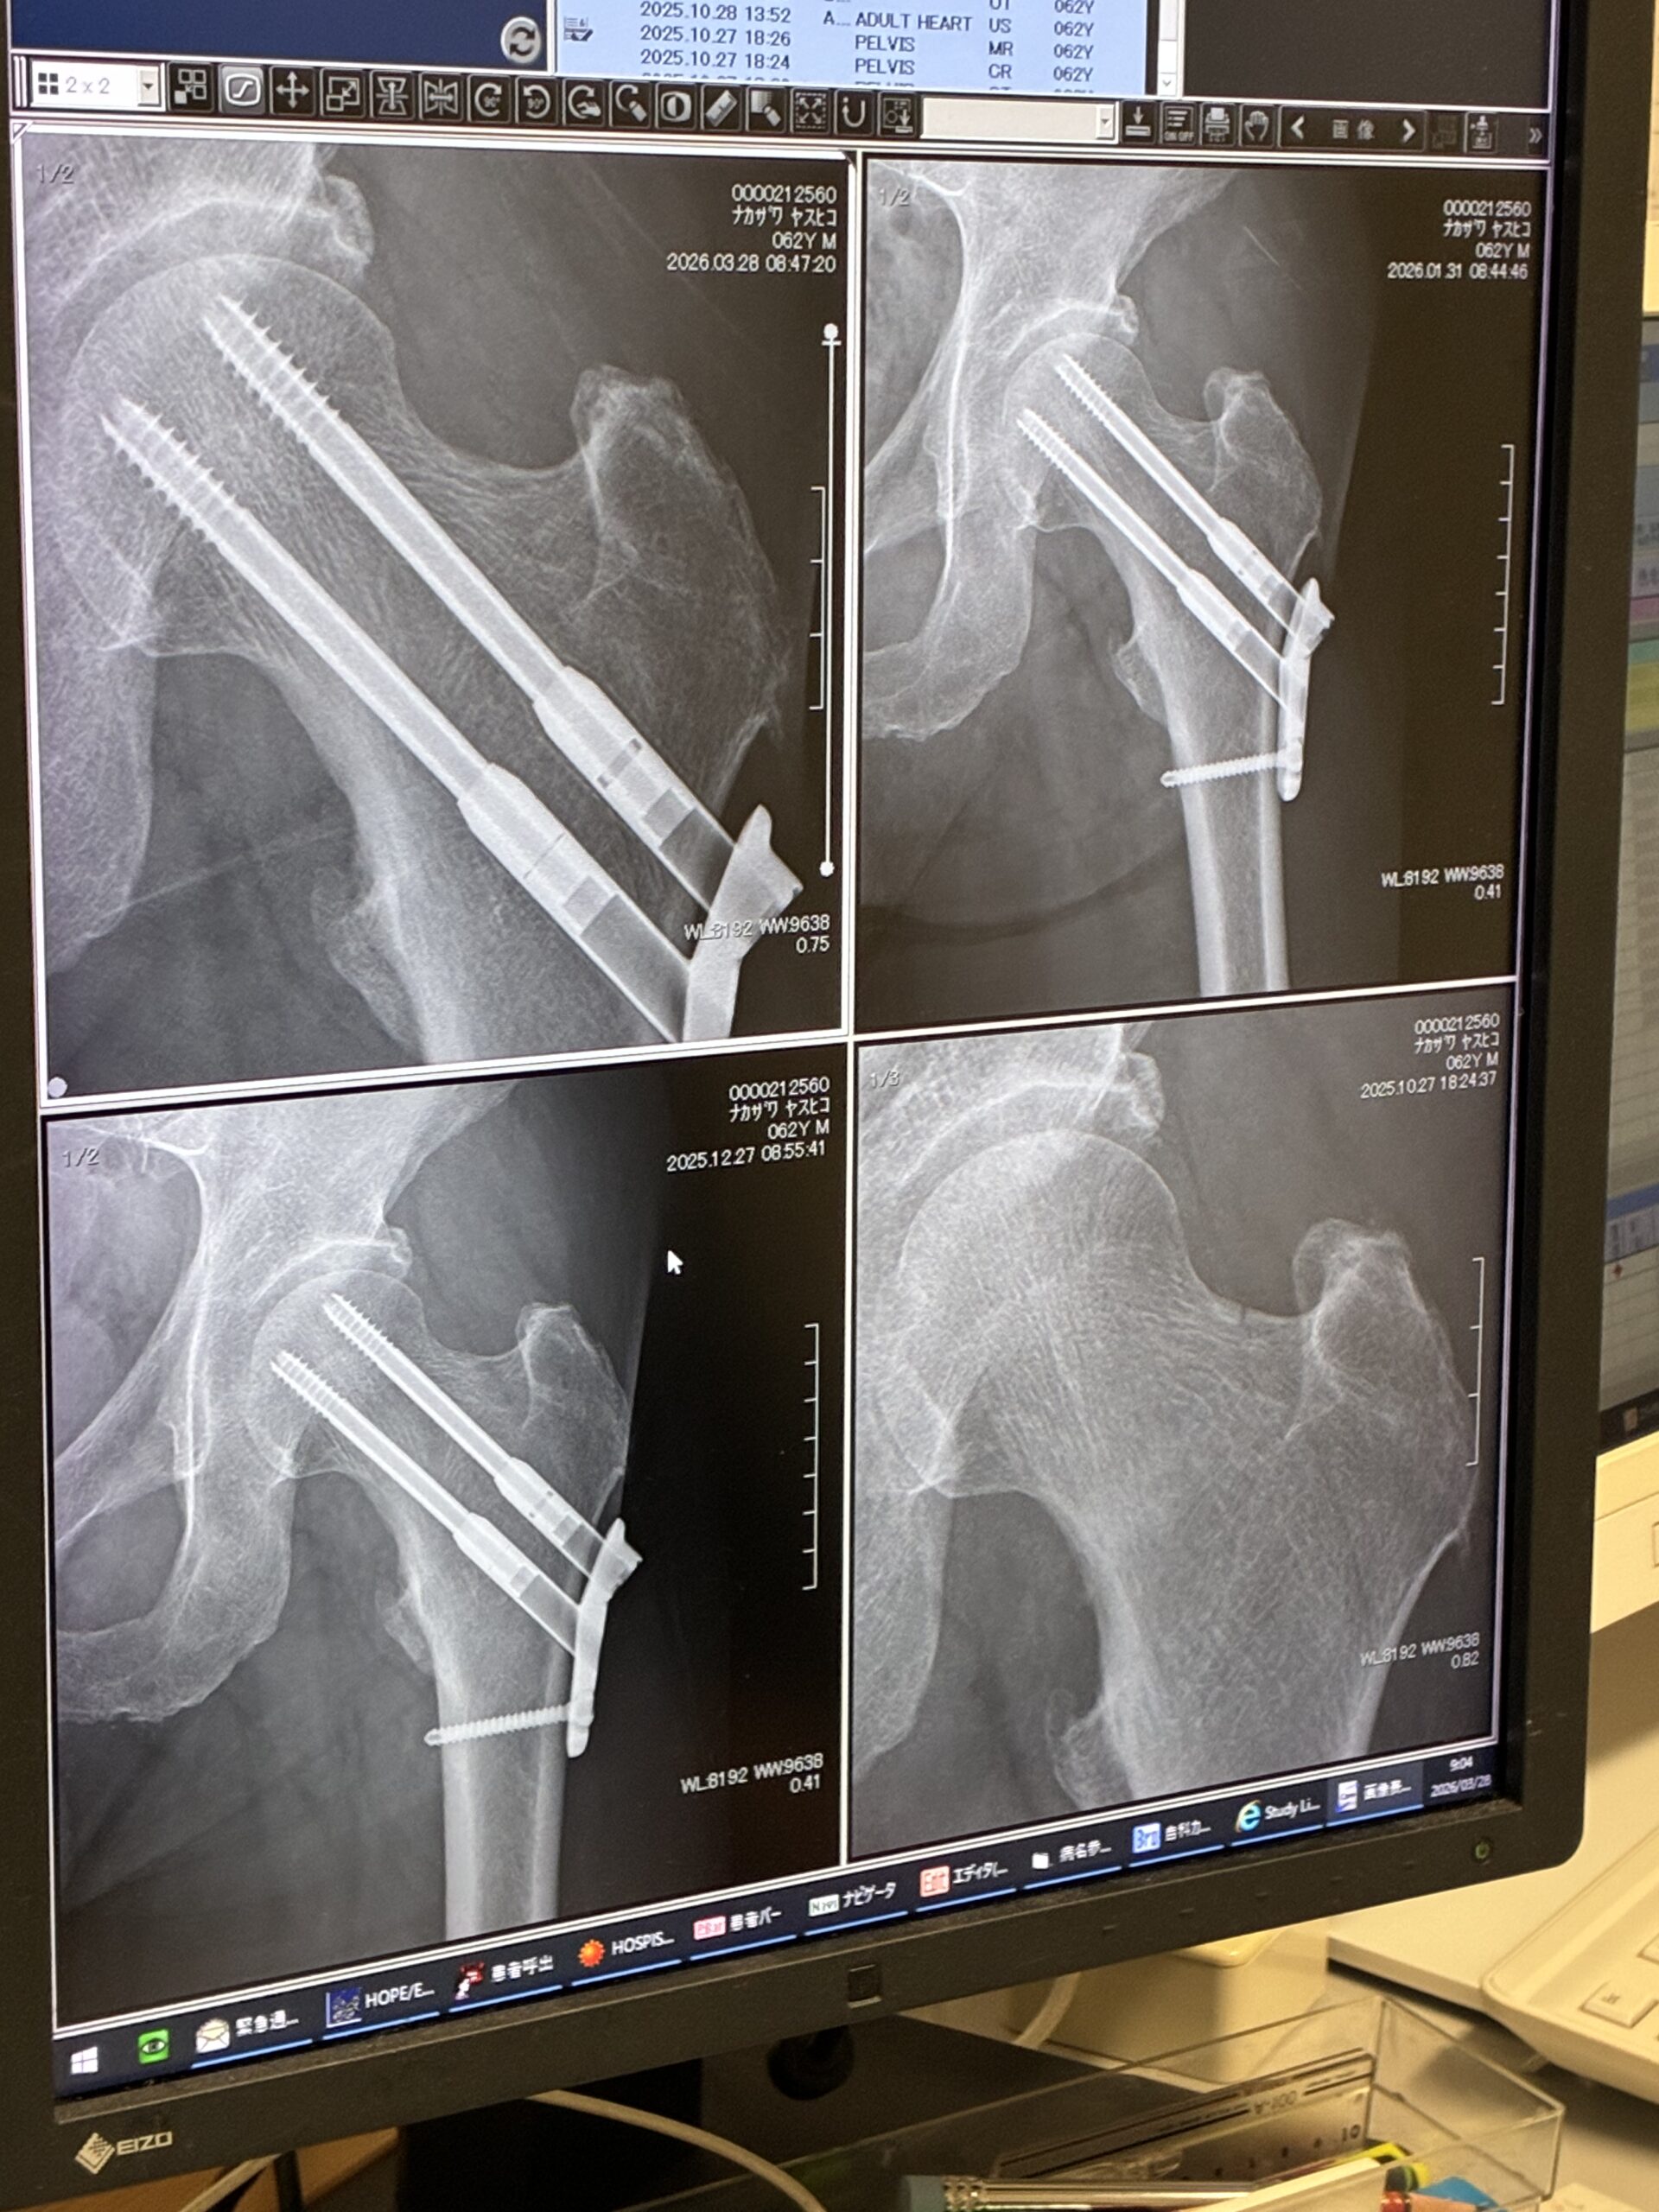

手術後5か月の検診に行ってきました。

レントゲンを撮って、手術をしてくれた先生に経過を観察してもらうわけだけど、骨折部はきちんとつながっているので、運動も普通にして良いと言ってもらえました。

ただし、大腿骨警部が疲労骨折をするなんてそもそもとても珍しいことらしいです。なので先生は僕がよっぽど無茶をする奴だと思っているみたいで「くれぐれも無理しちゃダメ。軽く運動する程度にしておきなさい。」と念を押されました。そして次回は3か月後に経過を見せに来るようにと指示されましたが。とにもかくにも運動の許可をしてもらえたのは良かったです。